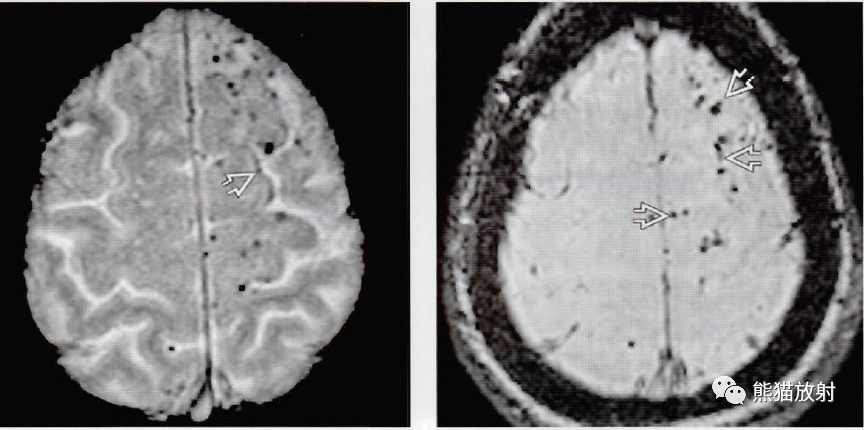

淀粉样变性脑血管病的影像诊断